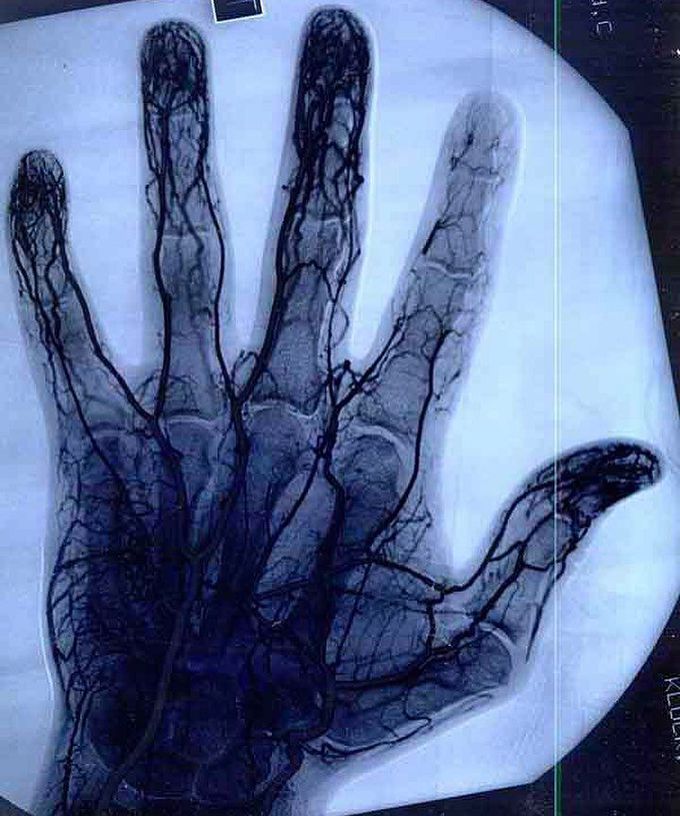

Hand angiogram

Hand angiogram of a professional Yoyo-ist showing the ruined veins of the right index finger. This happens when a yoyo string is wrapped around that finger and is chronically preventing the blood flow properly.